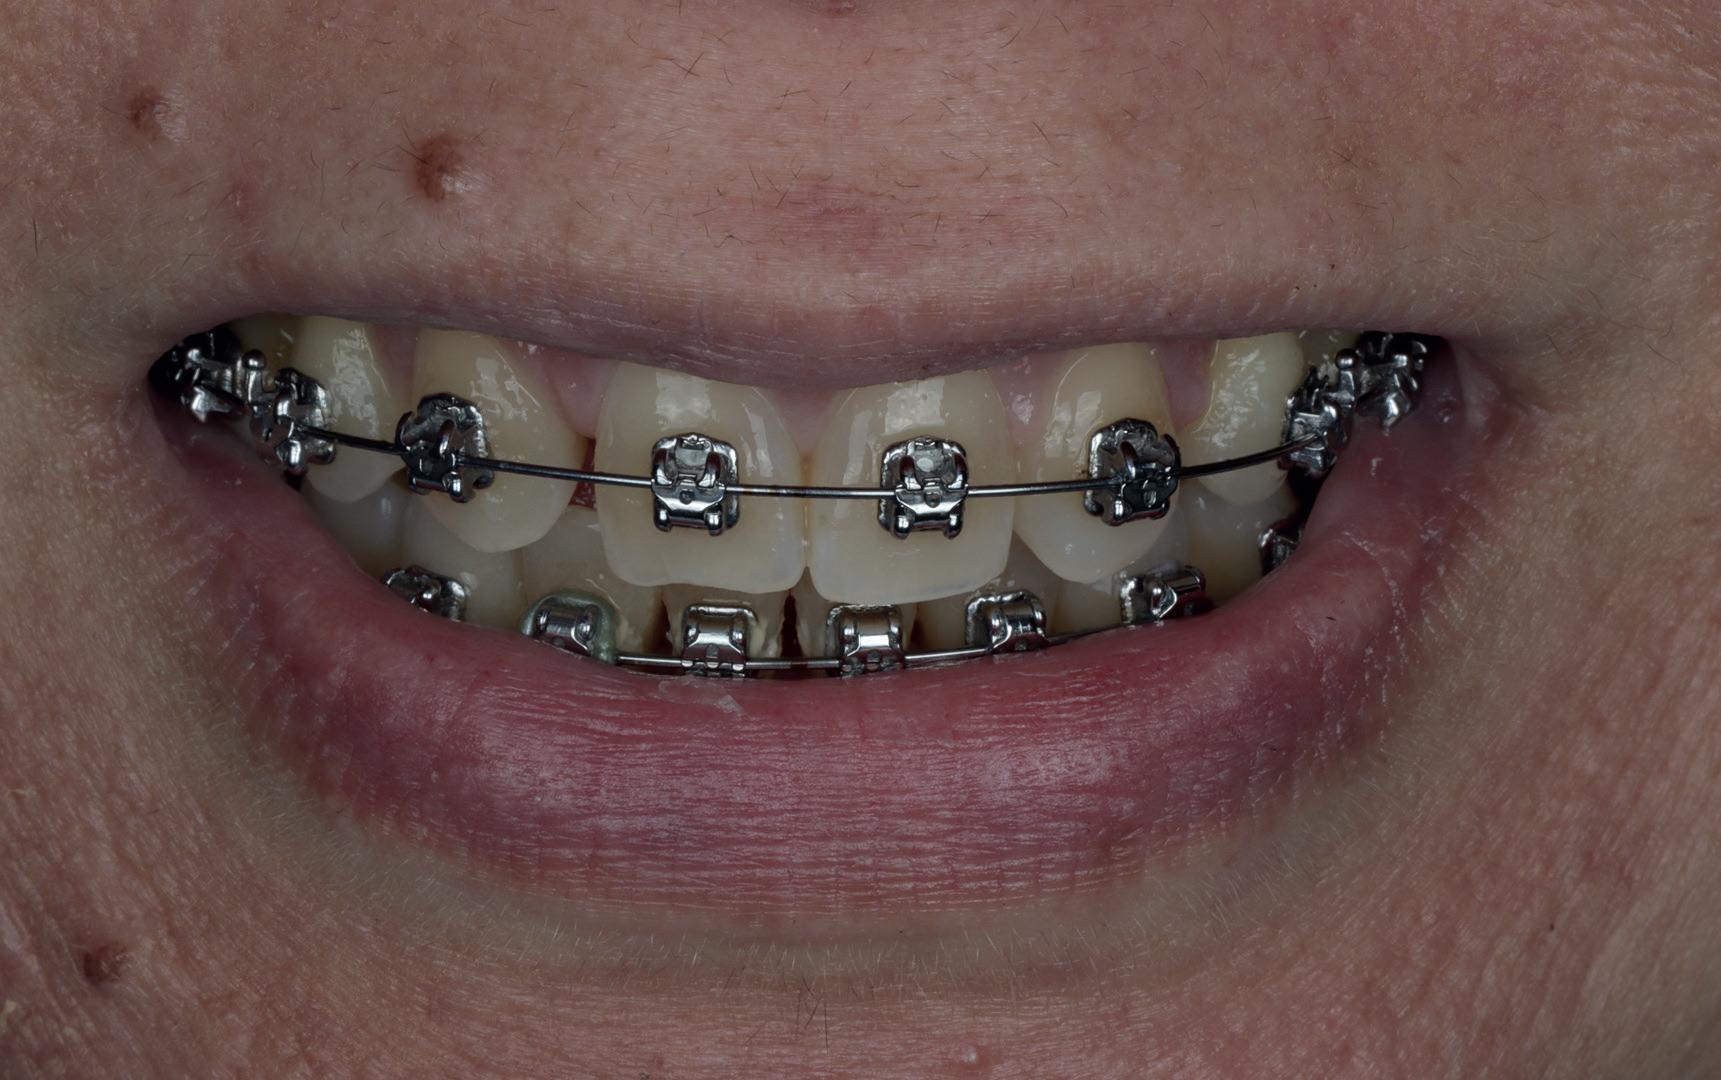

Een 47-jarige vrouw wordt aan het einde van het orthodontische traject door haar eigen tandarts naar mij verwezen voor een intake en eventuele behandeling. Bij mevrouw zijn elementen 12 en 22 afwezig. De 13 en 23 zijn gemesialiseerd. Haar eigen tandarts vraagt of ik het front met composiet kan restaureren om weer een harmonieuze glimlach te krijgen (Afbeelding 1).

Tijdens de intake wordt een complete lichtfoto status gemaakt om de positie van de elementen goed in kaart te brengen en een behandelplan op te kunnen stellen. Op de close-up foto van het bovenfront (afbeelding 2) zien we dat er sprake is van slijtage aan element 11. Elementen 12 en 22 zijn afwezig en elementen 13 en 23 zijn gemesialiseerd. Tussen element 11 en 13 is er sprake van een diasteem. Dit diasteem is niet aanwezig aan de andere zijde (afbeelding 3).

Dit zorgt voor een lastige situatie, omdat bij het sluiten van dit diasteem (dit is de wens van de patiënt) elementen 13 en 11 breder zullen worden dan elementen 21 en 23. Dit is één van de redenen waarom ik patiënten altijd graag aan het einde van het orthodontist traject wil zien. Op dat moment is het nog mogelijk om kleine wijzigingen door te voeren, voordat de beugel definitief wordt verwijderd. Na de intake stuur ik een terugrapportage naar de orthodontist waarbij ik vraag om de elementen zo te positioneren dat de ruimte beter verdeeld is.

Ik zie mevrouw een aantal weken later terug voor evaluatie (afbeelding 4). Er is een klein centraal diasteem ontstaan en daardoor is het diasteem tussen de 11 en 13 ook kleiner geworden. Tussen de 21 en 23 is geen diasteem aanwezig (afbeelding 5), waardoor er hoogstwaarschijnlijk wel iets breedte verschil zal zijn tussen de linker- en rechterzijde.

Met composiet wordt een snelle mock-up gemaakt om te beoordelen of ik in deze situatie goed kan uitkomen met de ruimte, of dat we wellicht de elementen nog meer moeten verplaatsen (afbeelding 6). Mevrouw is zeer tevreden met de snelle mock-up en daarom wordt besloten dat de orthodontische behandeling afgerond kan worden. Eventuele verschillen in breedte kunnen we proberen optisch zoveel mogelijk te maskeren.

Nadat de vaste apparatuur verwijderd is (afbeelding 7 en 8), zie ik mevrouw voor het maken van een afdruk/scan ten behoeve van een wax-up. Aangezien ik in deze casus wil werken met de injectietechniek, is een wax-up noodzakelijk.

1: Glimlach foto om de positie van de elementen ten opzichte van de lippen te beoordelen.

2: Close-up foto van de voortanden in de bovenkaak.

3: Occlusale foto om de positie van de elementen en de diastemen te beoordelen.

4: Situatie na orthodontische aanpassingen.

5: Occlusale foto om de nieuwe positie van de elementen te beoordelen.

6: Snelle mock-up met composiet om te bepalen of de huidige stand van de elementen de ruimte biedt om de elementen in de juiste vorm op te bouwen.

7: Glimlach foto na verwijderen van de vaste apparatuur.

8: Close-up foto van voortanden na verwijderen vaste apparatuur.